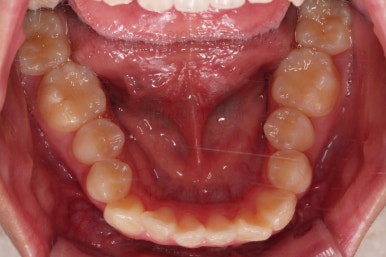

초진 시, 입 안의 모습입니다.

치아가 많이 삐뚤어요.

공간이 부족해서 앞니가 앞으로 많이 뻐드러졌고, 삐뚤한 양상 때문에 덧니가 되었네요.

어금니 맞물림도 좋지 못한 앵글씨 2급 부정교합 상태였어요.